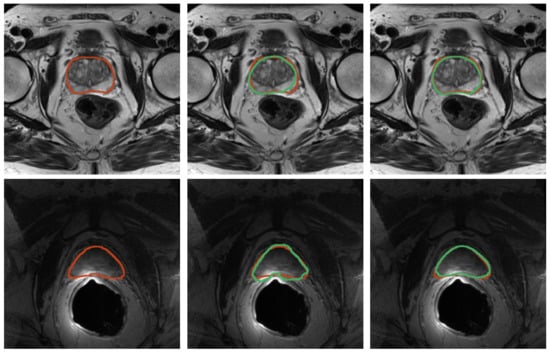

3.2. Registration

Quantitative results for registration across the two considered imaging modalities, TRUS and MRI, are reported in Table 4 for the configurations with and without landmarks, respectively. An example of the workflow for the image fusion is depicted in Figure 10. Dice Coefficient is higher than 91% for all the cases, and HD is less than 4 mm, demonstrating that the developed registration method is promising.

Figure 10.

Workflow employed for the image-fusion procedure. Segmentation masks are obtained for both domains—TRUS and imaging. Then, the registration is performed as described in Section 2.5, so that images can be fused. Both masks are shown after the registration procedure.